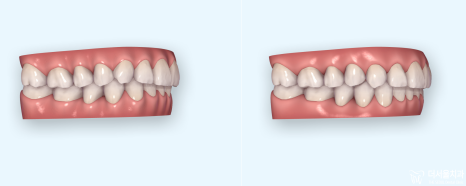

해당 시뮬레이션은, 인비절라인 장치를

선택하셨을 때 보여드리는 클린첵 이라는 겁니다.

구강 스캐너 아이테로

사진처럼, 치아가 얼마나 그리고 어떤 방향으로

이동이 되는지 미리 알 수 있는 시뮬레이션입니다.

그래서 이런 방법을 쓰게 되면, 치아교정 과정 을

설명 드릴 때 환자들께서 훨씬 더 이해를 잘

하실 수 있는거죠.